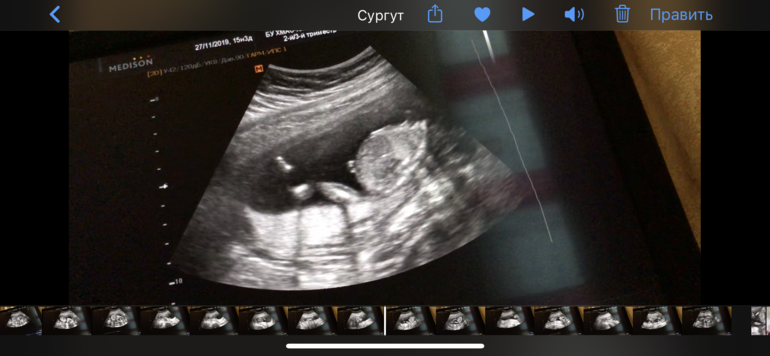

Пол по узи. 👶🏼 Или 👧🏼

Пол малышаА давайте посмотрим, кто же это может быть? Пацан или девочка? Врач пол не сказала, сказала ждите скрининг

Предлагаю поломать глазки, как думаете, кого ждём?))